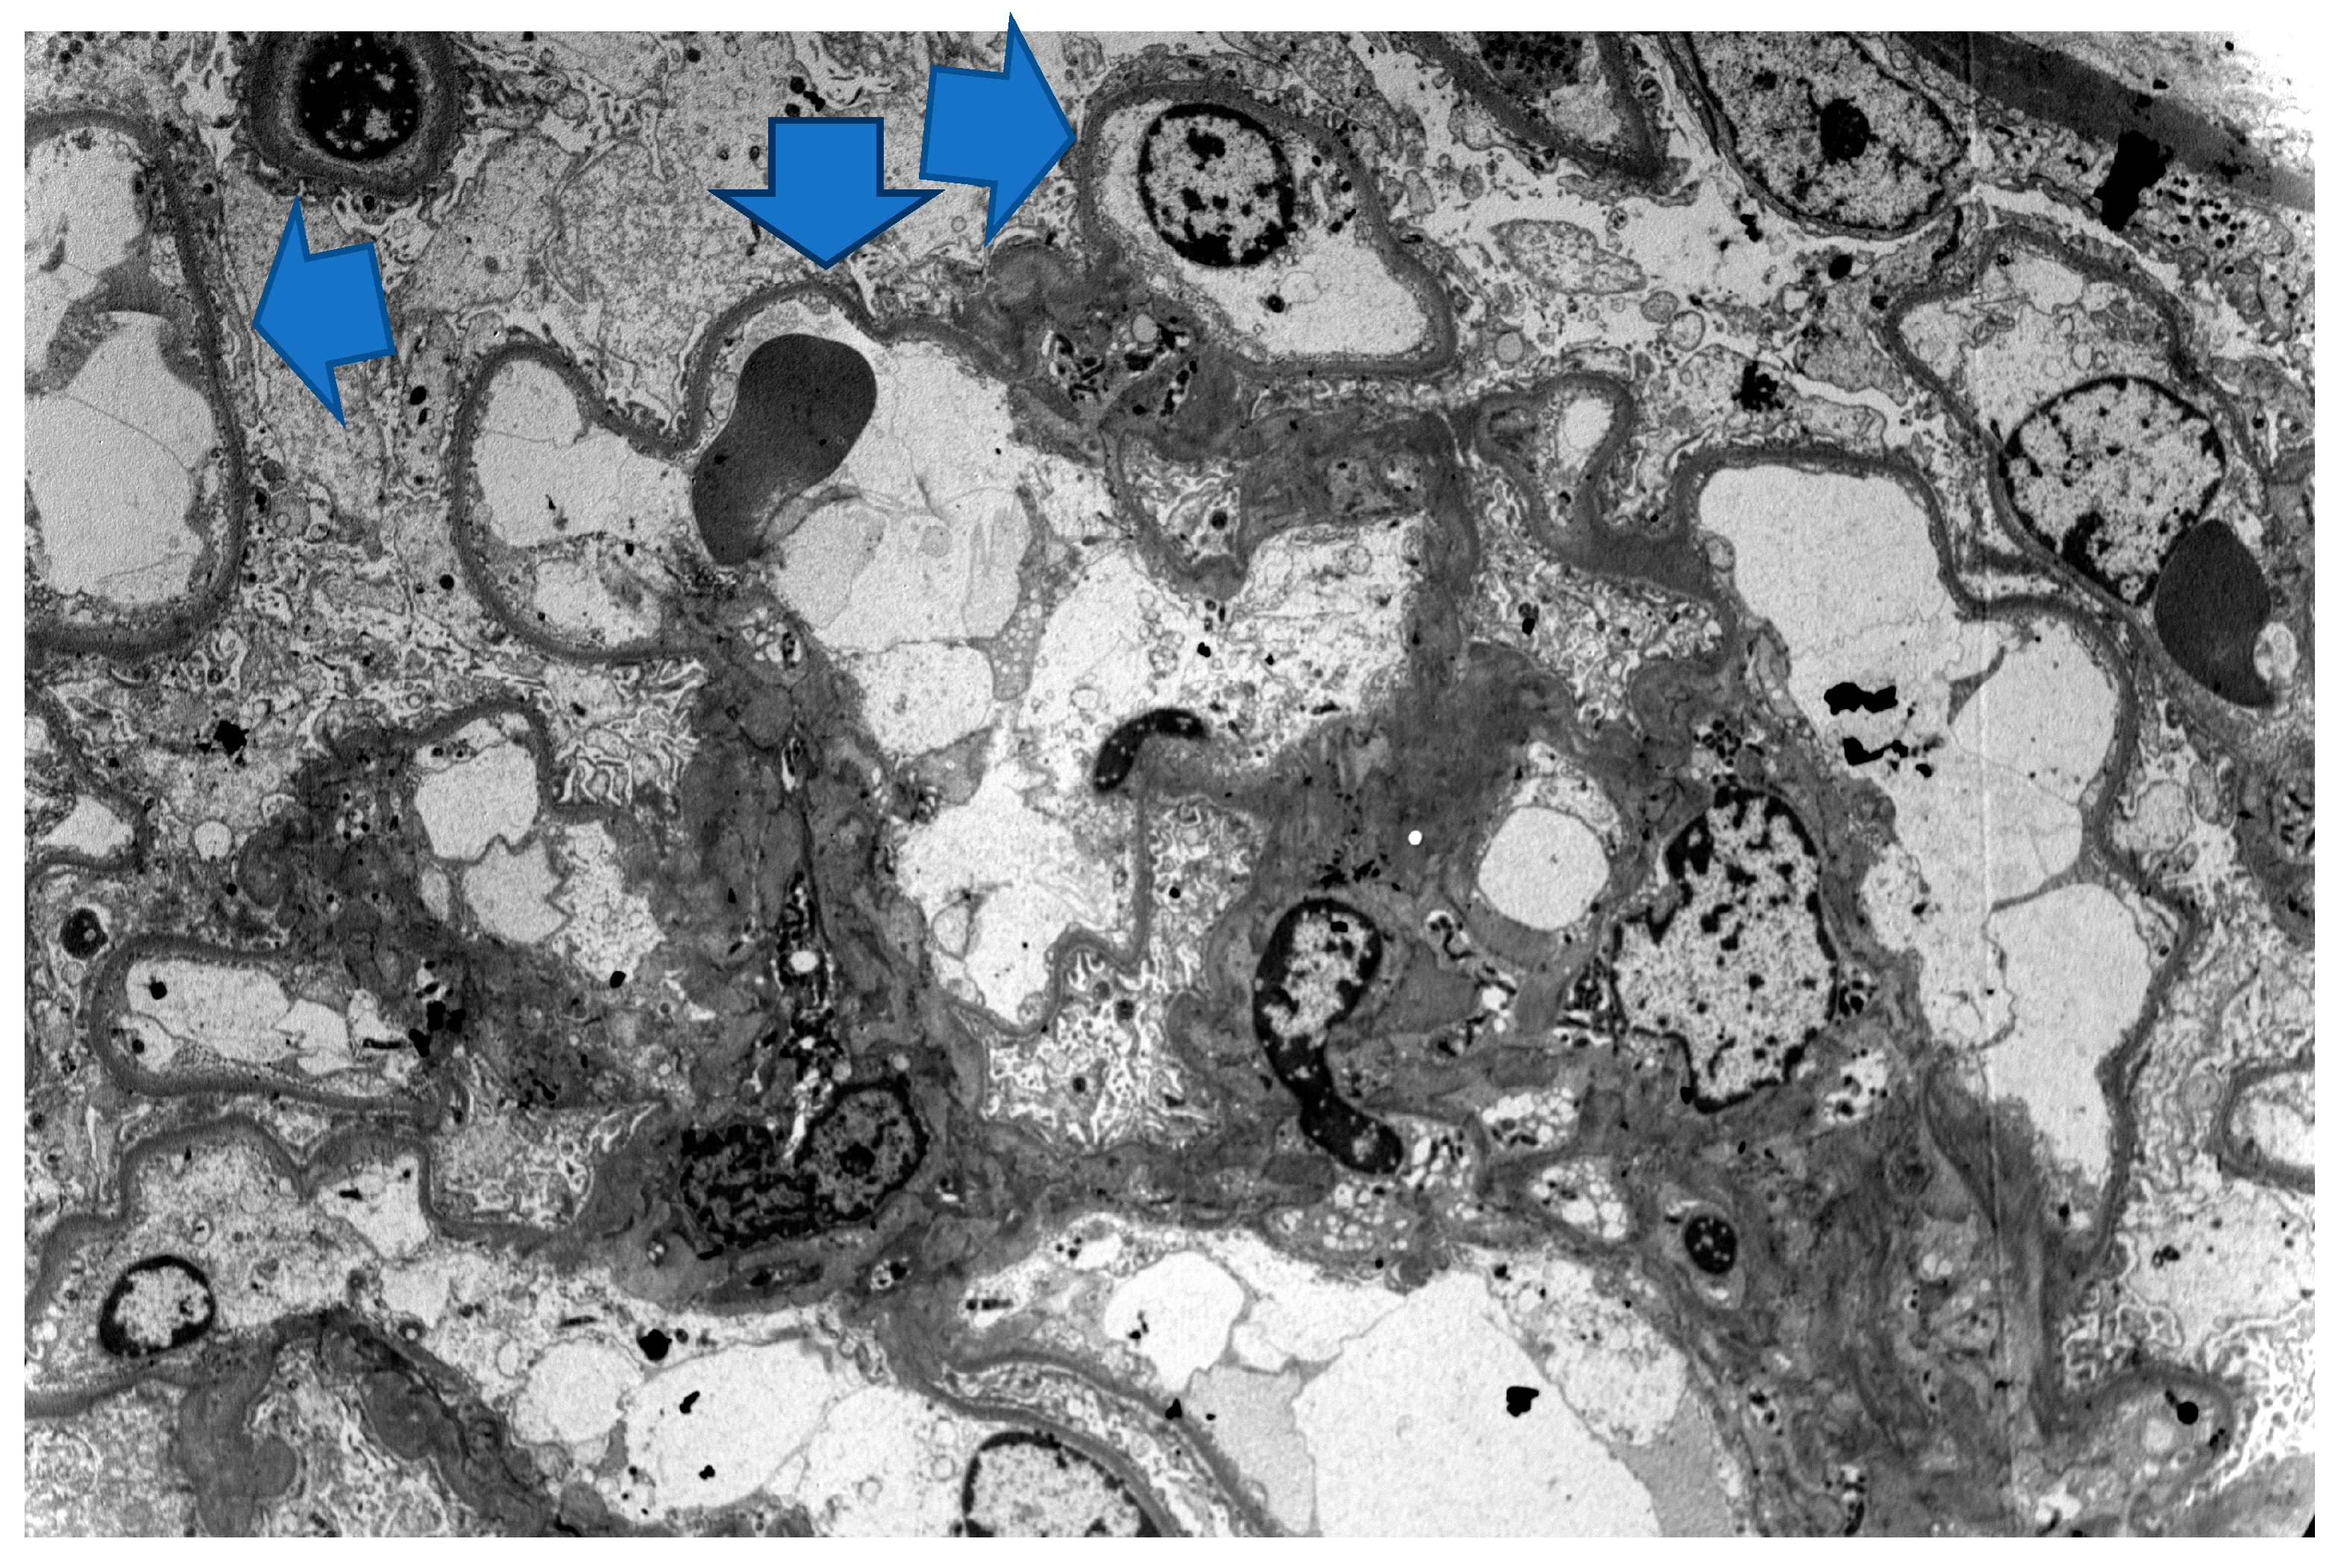

3. Case 2 Description: MCD Associated with D-Penicillamine

4. Case 3 Description: D-Penicillamine-Associated MCD